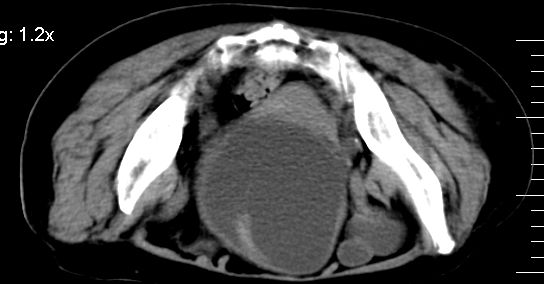

补充一下,谢谢提醒!

1.膀胱后壁见不规则致密影,随体位改变,为膀胱内凝血块;

2.双侧输尿管下段扩张.输屎管结石可能大。建议作进一步检查。

2.双侧输尿管下段扩张.输屎管结石可能大。

双侧输尿管下端扩张,并膀胱内血凝块 输尿管下端结石

2.双侧输尿管下段扩张,临床有血尿病史,建议进一步检查,找出血原因。